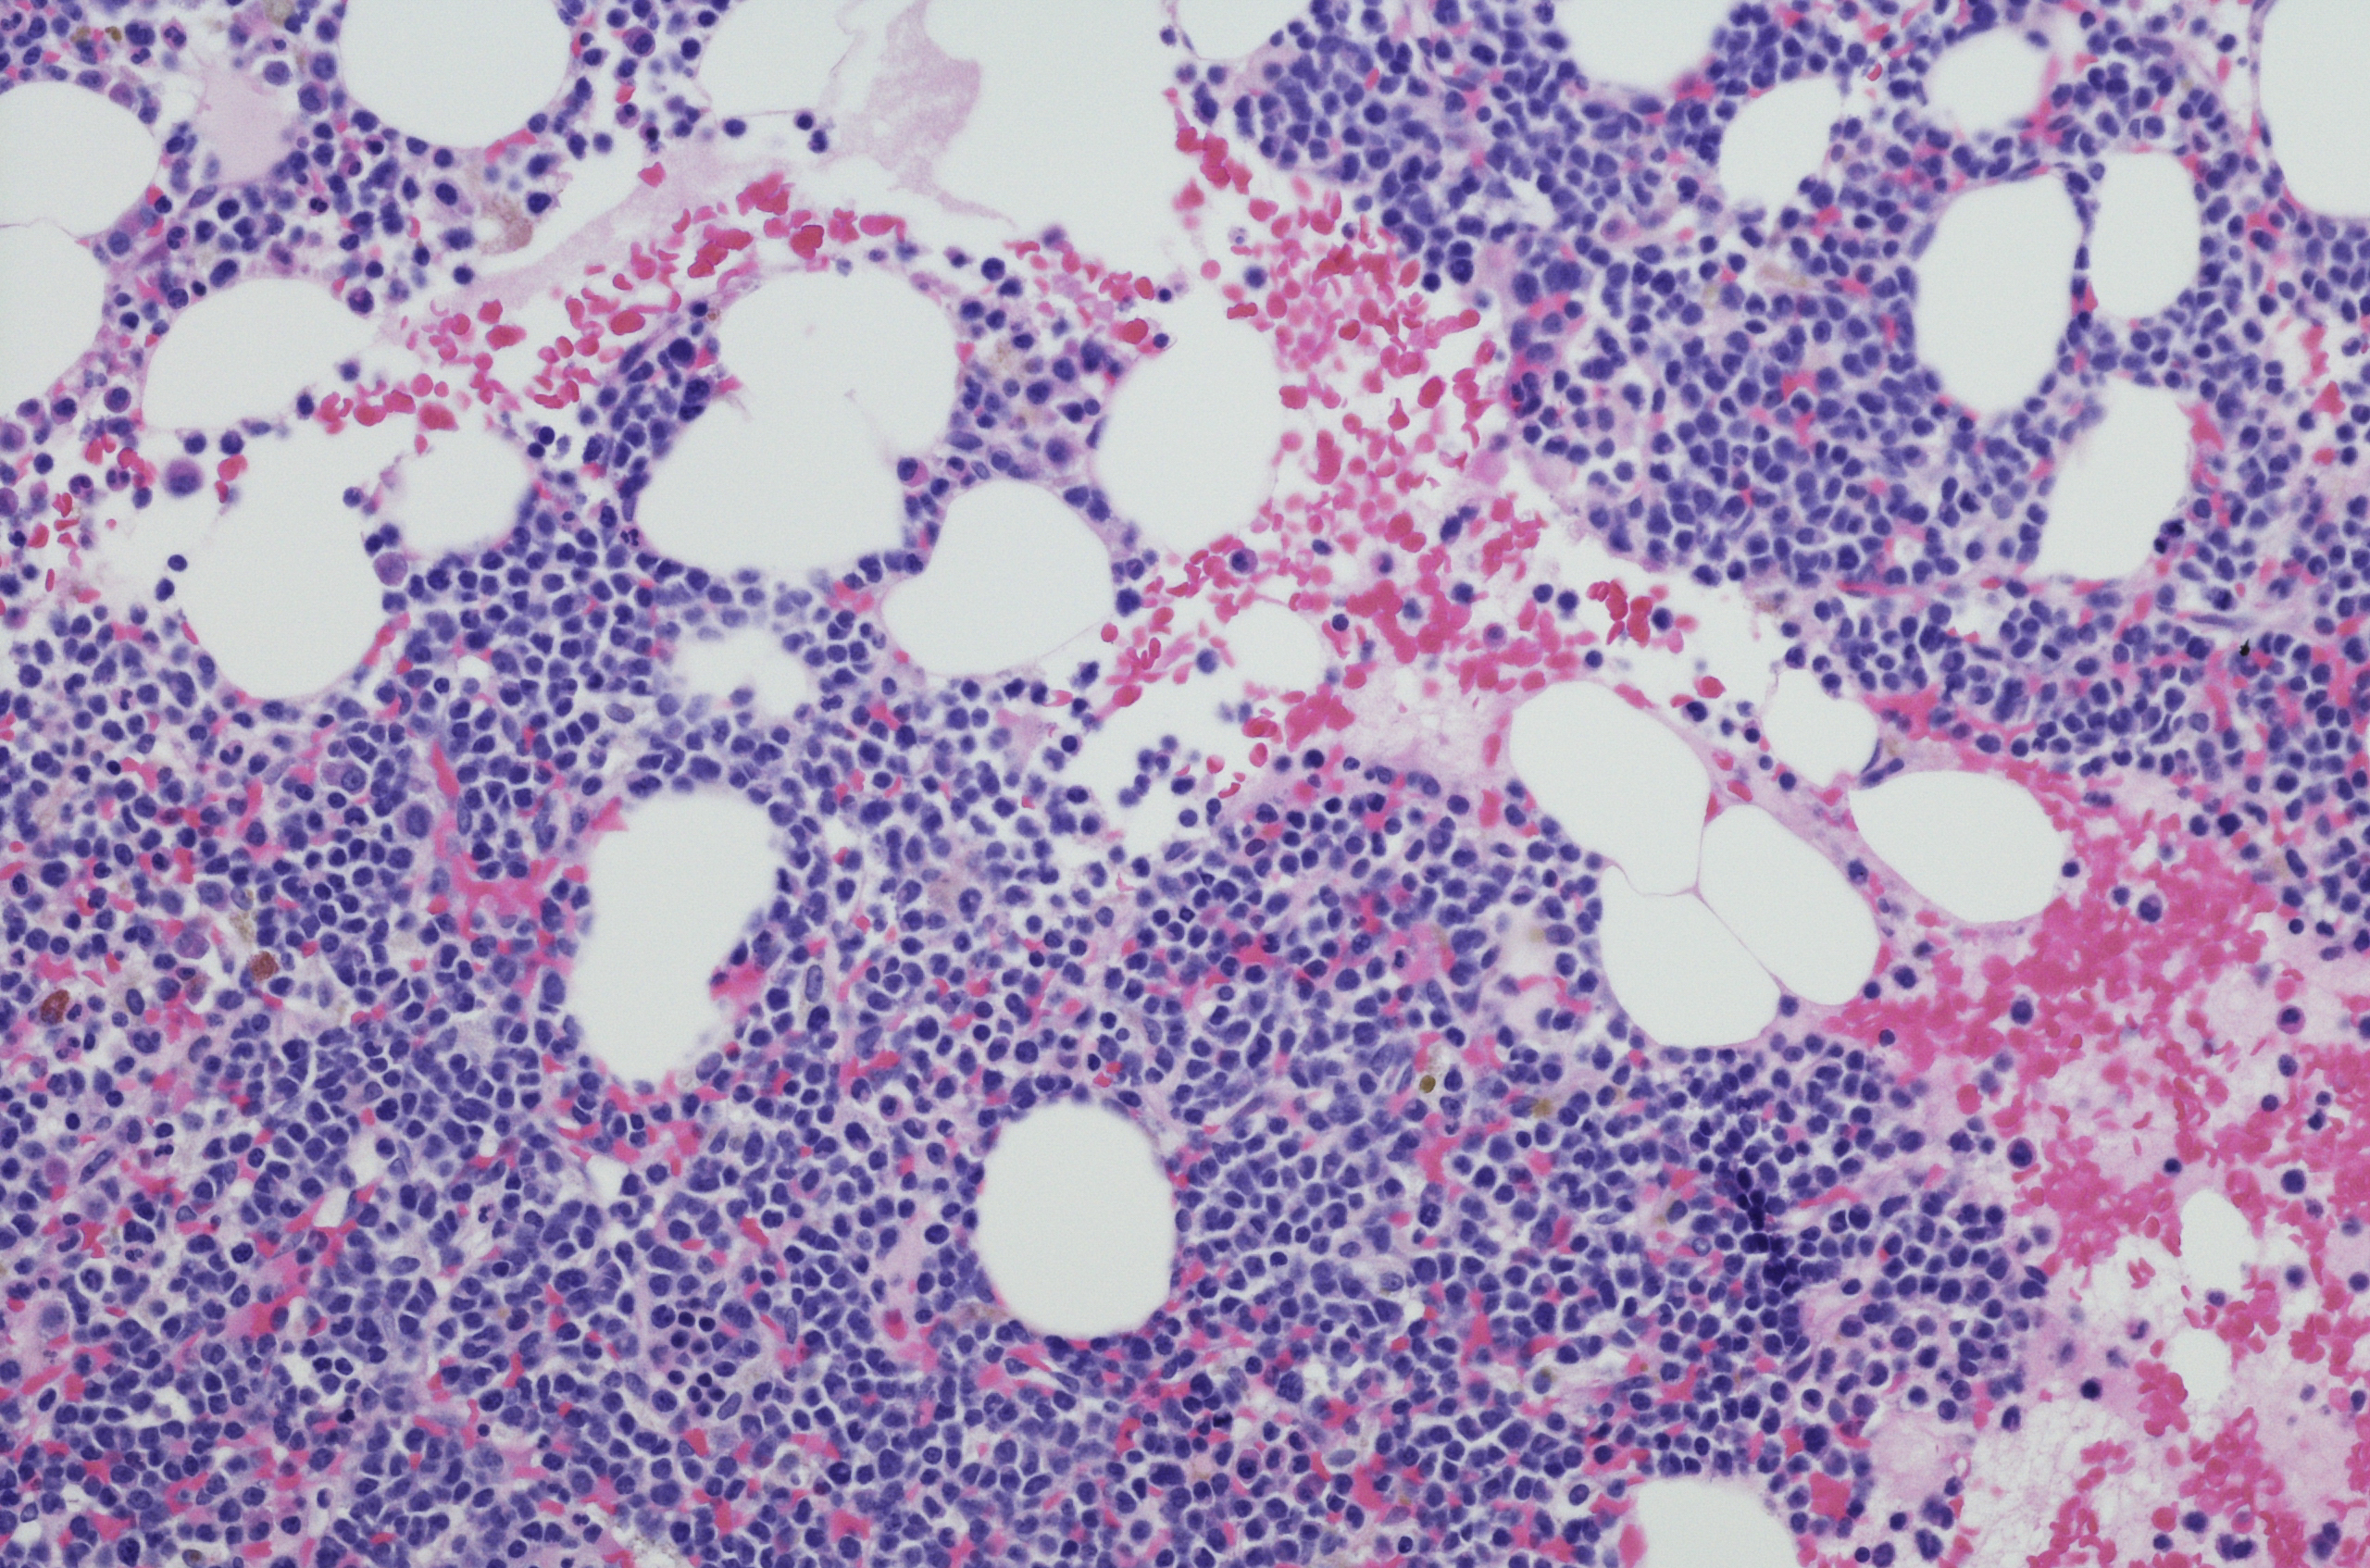

Su causa es desconocida. Se trata de una neoplastia hematológica (la segunda más frecuente) que se caracteriza por la proliferación clonal descontrolada de células plasmáticas anormales en la médula ósea. Representa entre el 1% y el 2% de todas las muertes por cáncer y, a pesar de los avances en el tratamiento, continúa siendo incurable. Todos los pacientes acaban recayendo y con cada recaída sucesiva las posibilidades de respuesta y su duración suelen reducirse.